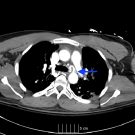

The causes of foot drop or lumps around the knee can sometimes be challenging to diagnose in the primary care or internal medicine setting. This article aims to describe one cause of both conditions.